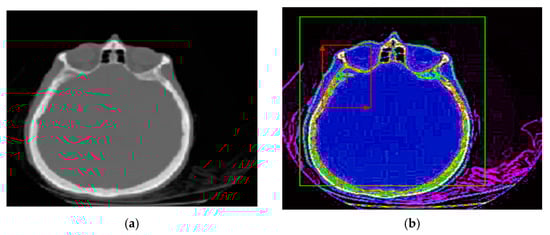

The proposed method for improving images with modified Wiener filter and nonlinear cellular network can be applied with success also with low contrast CT (computer tomograph) images. The improvement of tomographic image quality aims at obtaining superior visibility of the image components, the adaptive increase of the contrast, in order to be interpreted as easily as possible by the specialist doctor. Figure 7, Figure 8 and Figure 9 show the results obtained in the case of such images.

The interest in such filters is determined by the fact that much of the existing information in the images is provided by contours, and most of the noise removal methods cause them to fade. In the present case, at the cost of removing a smaller amount of noise in the contour-containing regions, it can be better preserved, as shown by the results shown in Figure 7, Figure 8 and Figure 9. There is thus a trade-off between the amount of noise removed and the quality of preserving the contours in the image.

It should be noted that in the results presented in Figure 8 and Figure 9, the noise reduction is accompanied by an improvement of the contours of the processed image, leading to a microscopic analysis, highlighting very well the contours of tumor formations from diseased tissues to healthy tissues. Such an estimate is useful for the medical act, especially for surgery. Additionally, the proposed method, in addition to the contour enhancement property, highlights the deconvolution applications for removing or reducing the blurring of energy areas in images by highlighting their vascularization elements (Figure 8 and Figure 9).

Imaging techniques are especially useful for interpreting biomedical CT/MRI images. The improvement of the quality of the tomographic images aims at obtaining a superior visibility of the image components, the adaptive increase of the contrast, to be interpreted as easily as possible by the specialist doctor. In the case of CT images, when the contrast is satisfactory ( λ = 0.05 ) , it is necessary to preprocess the image using the Wiener filter proposed in the article and nonlinear cellular network. Thus, image analysis after edge detection in preprocessed images can be facilitated. Based on the presented results, the validity of the proposed method for improvement of medical images can be found by the simultaneous use of the modified Wiener filter described in the article and cellular neural networks, for concrete applications in CT medical imaging.

Figure 7. (a) Initial image with low contrast; (b) improved image—CT cranial layer image processed with modified Wiener filter.